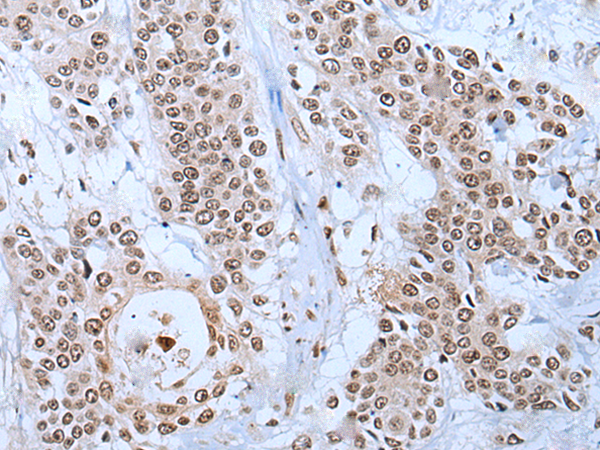

分类: 科研抗体货号: P05985别名: HCNP; HCRN; SYF1; NTC90应用: WB,IHC反应种属: Human, Mouse, Rat